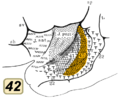

BA41. BA42

BA42 BA41. Inside lateral sulcus.

BA41. Inside lateral sulcus. BA42. Inside lateral sulcus.